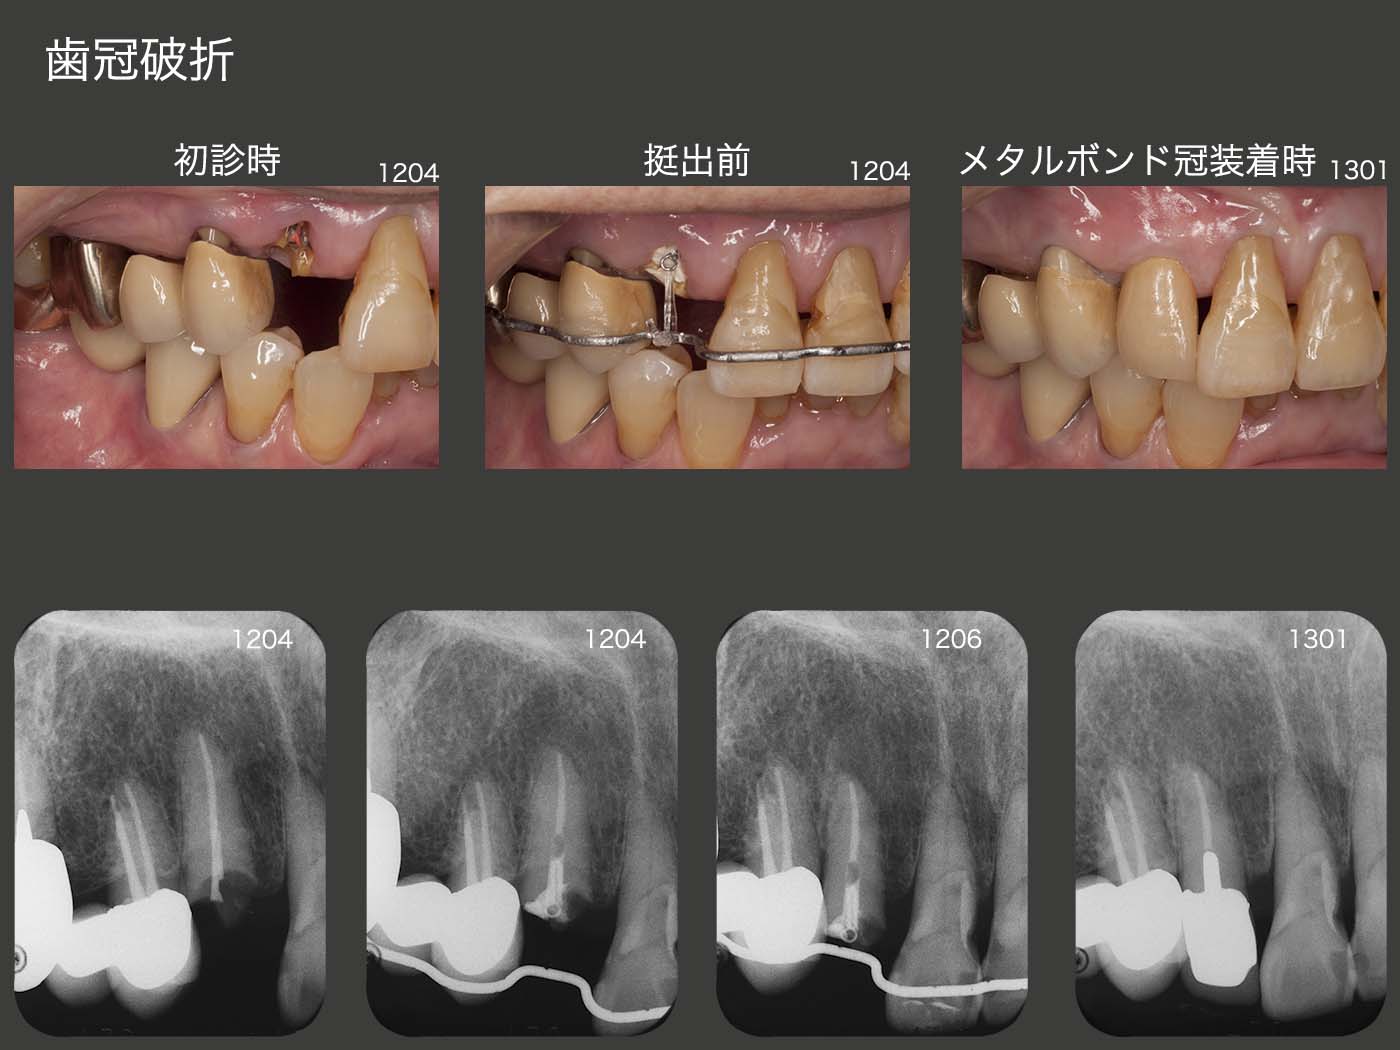

2012年4月初診、79歳の女性。右上3が折れたとのことで来院。歯冠部の歯質はないが、デンタルX線写真から歯根には十分な長さの歯質がある。もし抜歯となりブリッジを作製するとなれば、右上④5⑥の既存ブリッジを作り直すことになるし、ほぼ健全歯である右上1を切削する必要が生じる。このような大掛かりな治療を行わず、右上3の保存に努めるべきである。そこで、4月に矯正的挺出を開始し、6月に終了した。その後歯冠長増大術を行い、歯肉縁上歯質を確保した。暫く経過をみて特に問題が生じなかったので、2013年1月にメタルボンド冠を装着した。